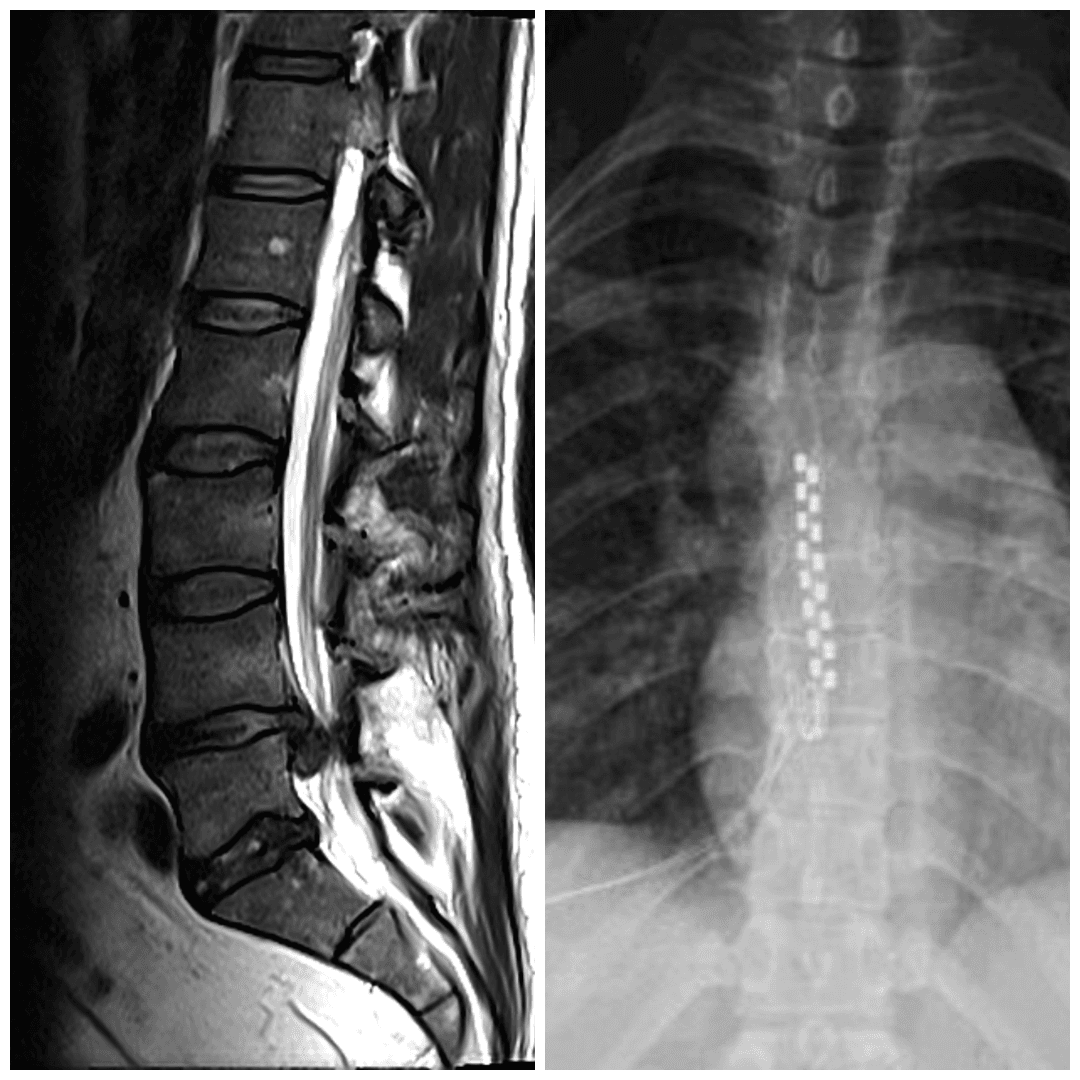

MRI is the diagnostic tool of choice for identifying disc injuries, providing soft-tissue detail that X-rays and CT scans cannot match. Utilize high-field 1.5T or 3T MRI to ensure optimal resolution and diagnostic clarity.

An MRI clearly visualizes:

- Disc herniations and their size/location

- Annular tears (high-intensity zones on T2-weighted images)

- Nerve root compression

- Spinal stenosis

- Facet joint arthritis

- Other structural abnormalities

But MRI shows anatomy, not pain. Connecting imaging findings to your symptoms requires clinical expertise. This is why the Deuk Spine Exam® combines MRI findings with pain history and physical examination, to determine which abnormalities on imaging are actually causing your pain versus which are incidental findings.